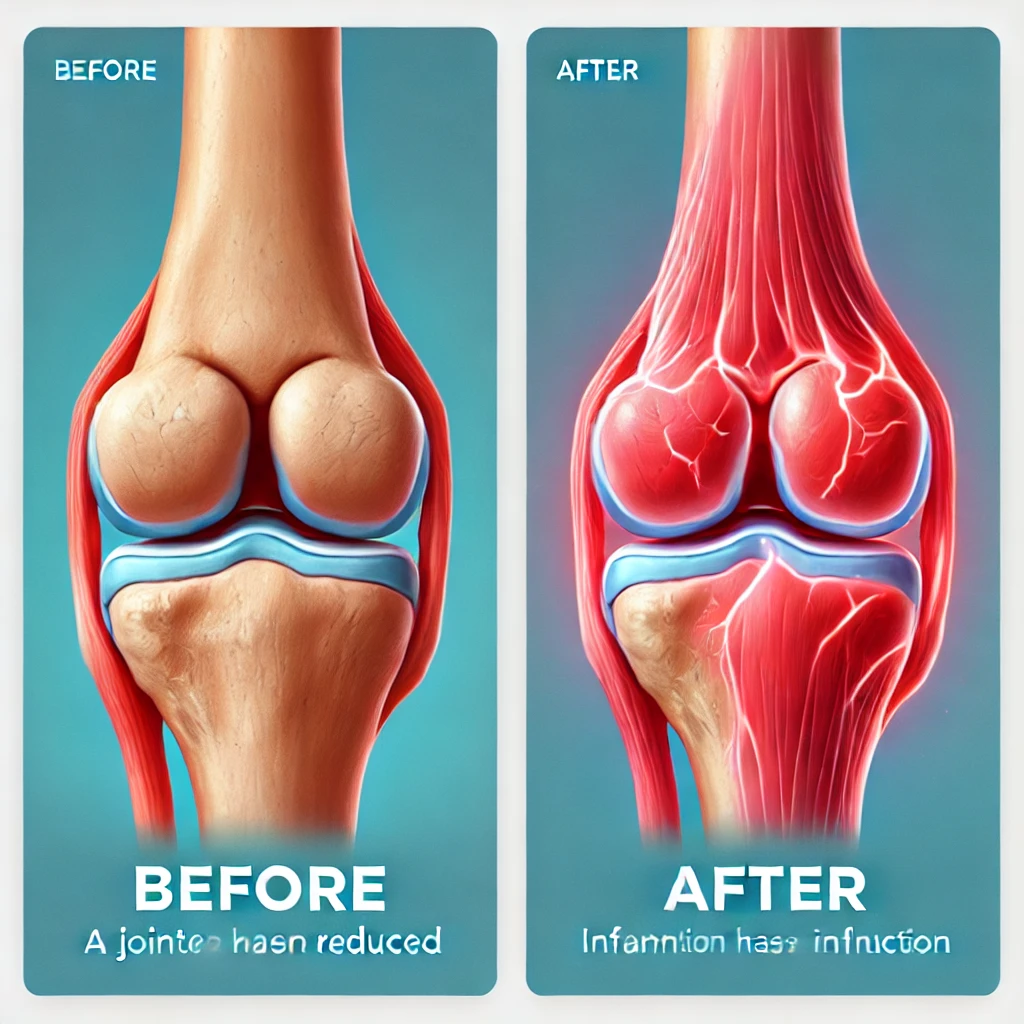

콘드로이친(Chondroitin)은 연골 조직의 주요 구성 성분 중 하나로, 주로 관절 건강을 지키는 데 중요한 역할을 합니다. 특히 나이가 들면서 연골이 손상되고 관절이 약해지는데, 이때 콘드로이친은 연골 조직의 회복을 촉진하고 염증을 억제하여 통증을 완화시켜 줍니다.

콘드로이친은 연골을 구성하는 중요한 요소로, 손상된 연골을 회복시키는 데 도움을 줍니다. 이를 통해 관절의 마모를 줄이고, 관절염과 같은 질환을 예방하는 역할을 합니다.

염증을 억제하는 효과가 있어 관절 통증을 줄이는 데 기여합니다. 지속적인 관절 통증으로 고통받는 분들에게 좋은 선택이 될 수 있습니다.